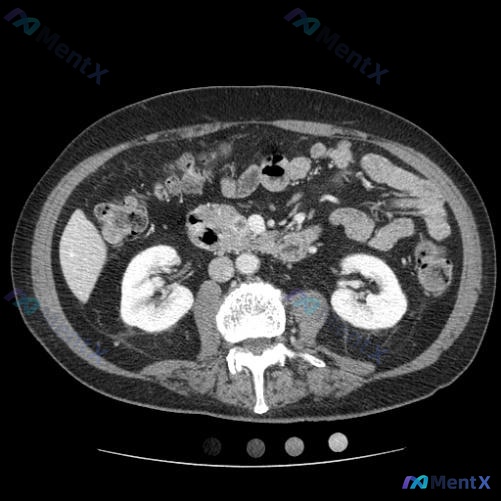

整理到一个病例,第一眼很容易被带偏—— 73岁女性,因评估良性肾病灶做公共卫生CT,结果被识别出“胰腺内偶发灶”,要求进一步做多相胰腺CT。 先看这份影像分析的核心客观表现: - 双肾、脾脏、腹膜后主要实质脏器(除定位外)未见明确局灶占位; - 重点是:肠系膜根部及周围脂肪间隙可见明显软组织密度影,...